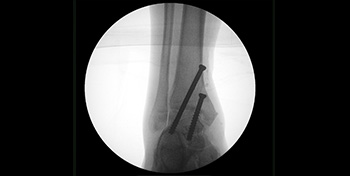

- Day 0 – X-rays obtained during surgery to ensure correct screw positioning.